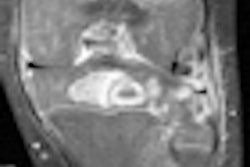

The study is among the first to provide gender- and age-specific data on the motions of the normal heart based on a regional analysis of myocardial velocities covering 16 segments of the left ventricle, the authors wrote in the study published online December 8.

The results, obtained with MRI tissue-phase mapping (TPM), provide the most precise measurements yet of the left ventricle's complex motions as it contracts and relaxes with each heartbeat.

The investigators used TPM to analyze segmental, 3D myocardial velocities with high temporal resolution (13.8 msec) to assess left ventricular motion.

Electrocardiogram-gated and respiration-controlled images were acquired on a 1.5-tesla MRI scanner (Magnetom Sonata, Siemens Healthcare, Malvern, PA) using a black-blood k-space segmented gradient-echo sequence (temporal resolution = 6.9 msec, flip angle = 15°, bandwidth = 650 Hz per pixel) with a spatial resolution of 1.3 x 1.3 mm. Data were acquired in basal, midventricular, and apical short-axis planes, with a slice thickness of 8 mm and temporal resolution of 13.8 msec.